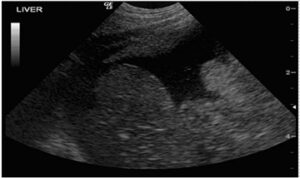

| Figure 1: A large volume of neoplastic effusion in a cat, likely due to a pancreatic mass. Liver lobes are visible. |